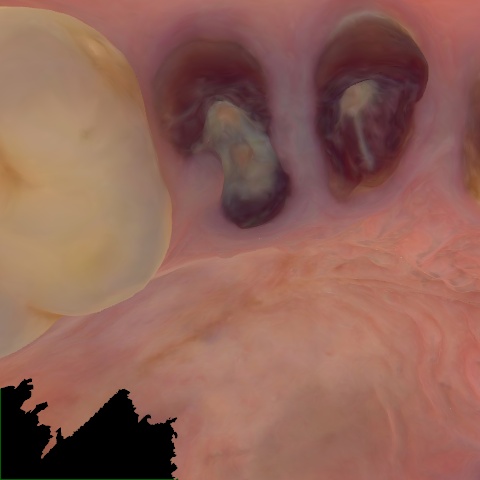

Incorrect Quality Level

The reference annotation for this image is

None

.

Please select the correct quality level.

Annotated as "Good"